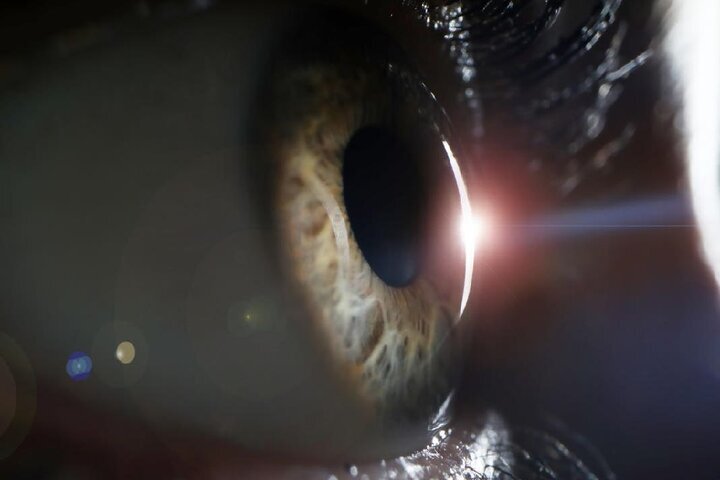

استراتژی تهاجم سلول

۱. ویروس به سطح سلول می چسبد، در آن وارد شده و توسط غشای سلولی احاطه می شود.

۲. پروتئین هایی که جهش سلول را پوشش می دهند غشا را باز کرده و اجازه می دهند RNA ویروس وارد سلول شود و شروع به همانندسازی کند.

۳. نحوه خروج از سلول به طور کامل درک و شناخته نشده است، اما به نظر می رسد که ذرات ویروس در سطح سلول جمع شده و بیرون می آیند و ممکن است با یک پاکت میزبان خارج شوند.